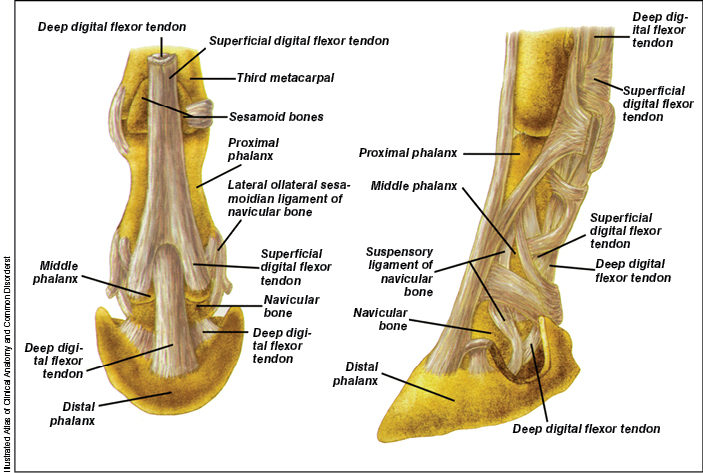

Navicular disease is a chronic, progressive degenerative condition that affects one or more of the components of the navicular apparatus, which includes the navicular bone, navicular bursa, deep digital flexor tendon and navicular ligaments. Usually, the condition will include more than one part of the apparatus.